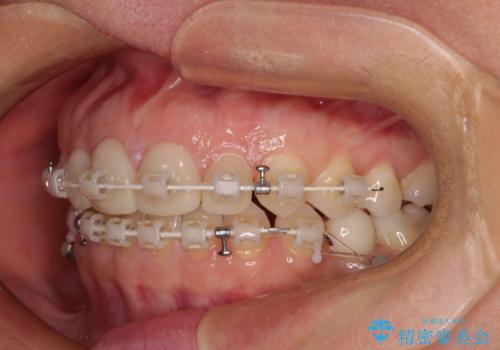

- 矯正装置

- 審美装置

下顎前歯は空隙歯列弓であったので、アンカースクリューとワイヤー装置を用いてスペースを閉じていくこととし、上顎前歯は矯正治療用の仮歯に置き換えた上で、仮歯の大きさを削って小さくしながら、上下前歯部の部分矯正を行うこととしました。